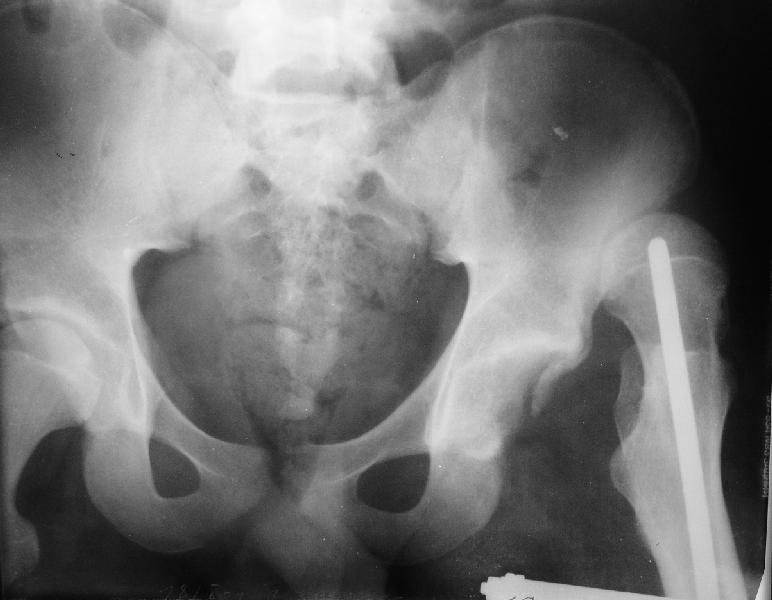

На мой взгляд, на ренгенограмме таза (левый сустав) имеется (имелось) перелом заднего края вертлужной впадины, перелом ацетабулум-вывих головки? (нужны дополнительные снимки).

Очень трудно угадать, когда вывих произошел: во время травмы или во время операции на бедре, хотя около 5% переломов бедра сопровождаются переломами шейки бедра, 15-60% с минимальными смещениями и до 30% первично не распознаются.

если проследить две линии: передний и задние края ацетабулум должны встречатmся с латеральной стороны ацетабулум, а у данного больного они формирует цифру "8", т.е. передний край ацетабулум расположен более спереди. Ацетабулум у этого больного немного в ретроверсии, т.е. задний край у него недоразвит и трудно удержать головку в cуставе после реконструкции.

Больной нуждается в дополнительных исследованиях: Ренгенограмму таза, Judet view левого сустава, бедро, голень и КТ ацетабулум. После этих данных можно подумать над этим ребусом, хотя согласен с

мнениями о физиологической низведении головки аппаратом, в этом случаи считаю метод Илизарова идеальным и надо начать сразу же.